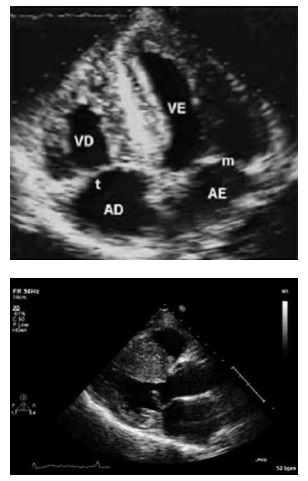

Um paciente de 41 anos de idade, hipertenso,

em uso de losartana, com queixa de dispneia durante os

esforços e desconforto precordial inespecífico nas últimas

semanas. Seguem imagens do ecocardiograma a seguir.

Com base nessa situação hipotética e nas imagens acima, assinale a alternativa que apresenta a etiologia adequada do quadro.